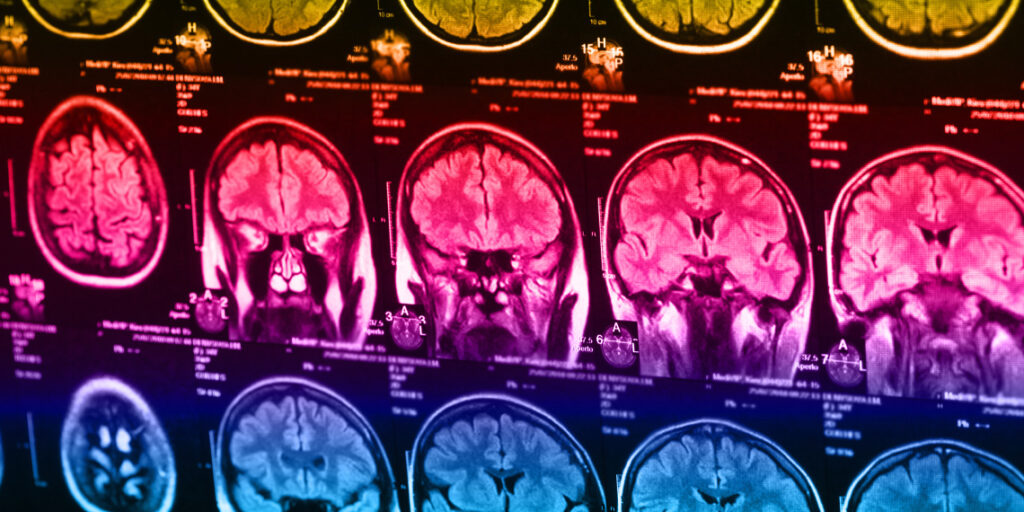

Os pesquisadores utilizaram a ressonância magnética funcional para medir a atividade cerebral. Essa tecnologia acompanha alterações no fluxo sanguíneo em diferentes áreas do cérebro, servindo como um indicador indireto da ativação neural. Durante o exame, cada participante realizou uma tarefa conhecida como paradigma Cyberball.

Os dados de neuroimagem revelaram diferenças claras na forma como os dois grupos processavam essa rejeição social. Em comparação com a fase de inclusão, o grupo com uso excessivo de smartphone apresentou um aumento significativo da atividade no córtex cingulado médio direito durante a exclusão, estendendo-se também ao córtex frontal superior direito.

O córtex cingulado médio é uma região do cérebro frequentemente associada ao processamento de emoções negativas. Ele faz parte da rede neural responsável pelo componente afetivo, ou desagradável, da dor. O aumento da ativação nessa área sugere que os usuários excessivos podem ter vivenciado a exclusão social como mais emocionalmente dolorosa ou angustiante.

Em contraste, o grupo controle apresentou um padrão diferente de atividade cerebral. Durante a fase de exclusão, esses participantes mostraram maior ativação no córtex parietal superior esquerdo, uma região mais relacionada ao processamento sensorial e ao gerenciamento da atenção do que ao processamento da dor emocional.